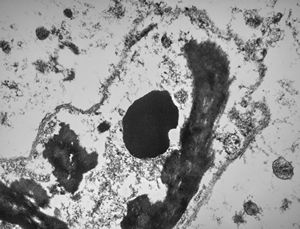

rabbit spinal cord trauma